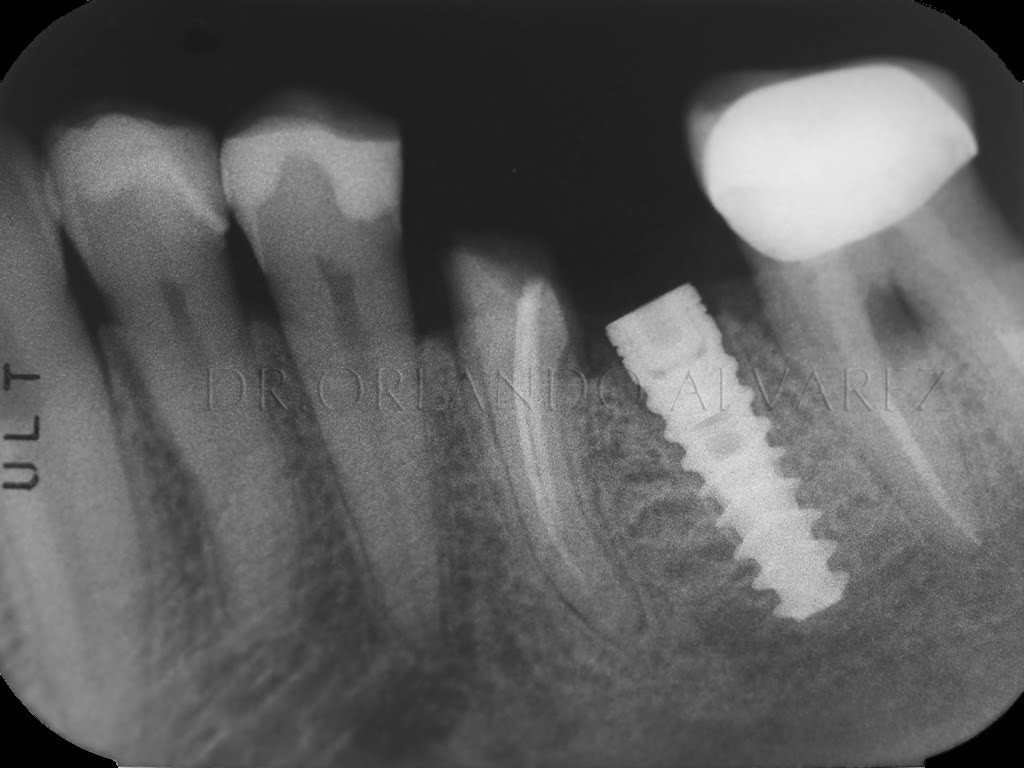

Una de las grandes ventajas aportadas por los sistemas CAD-CAM al mundo de la prótesis múltiple sobre implantes, es la mejora en la integridad de las estructuras conseguidas con un ajuste pasivo muy mejorado, gracias a los buenos ajustes marginales que son capaces de determinar. Del mismo modo que anteriormente se realizó en el epígrafe […]

Uno de los tratamientos más habitualmente desarrollados en el quehacer diario de la clínica dental pasa por la eliminación de espacios edéntulos unitarios o parciales, producto de las pérdidas dentarias por caries o enfermedad periodontal, entre otras causas. Normalmente, la tendencia actual pasa por la confección de prótesis cementadas, por sus ventajas en el ajuste […]